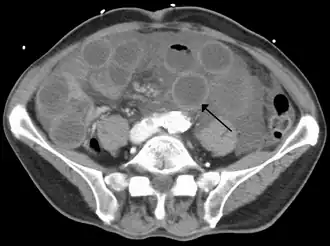

| tomografia computadorizada mostrando o intestino delgado dilatado com paredes afinadas (seta preta), mostrando características da isquemia do intestino devido a uma trombose da veia mesentérica superior. | |